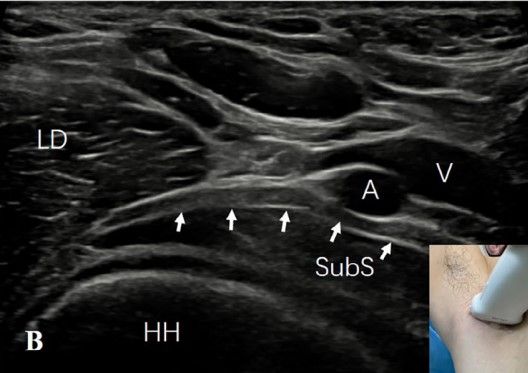

2)肩胛下肌的前方:患者平躺,肩部完全外展以暴露整个腋窝。探头水平放置在肱骨头上。观察到肩胛下肌位于肱骨头的上方,腋神经(AN)的短轴位于肩胛下肌和背阔肌之间,呈点状低回声(图3A)。旋转探头,显示腋神经在肩胛下肌表面的长轴切面,呈带样低回声(图3B)。

图3A:探头水平放置在肱骨头(HH)上。可见肩胛下肌(SubS)位于肱骨头上方。腋神经(AN)的短轴(箭头)在肩胛下肌(SubS)和背阔肌(LD)之间呈点状低回声。

图3B:旋转探头显示腋神经(AN)的长轴(白色箭),在肩胛下肌(SubS)表面呈低回声带。A,腋动脉;V,腋静脉

3) 腋动脉后方:探头沿腋神经向内侧移动至腋血管后方,有时可见腋神经由臂丛后束发出(图3C)。将探头与腋神经平行并轻调探头位置,可见旋肱后动脉位于腋神经旁,并可追溯至其起源于腋动脉(图3D)。

图3C:沿腋神经(AN)(白色向上箭)向内侧移动探头至腋动脉(A)和静脉(V)的后方。